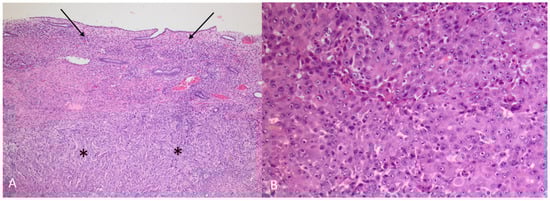

Figure 9. (A) HAC (asterisks) growing under intact endometrium (arrows) (Hematoxylin and eosin, 5×) (B) HAC (Hematoxylin and eosin, 10×). The tumour was a poorly differentiated adenocarcinoma, primarily growing in solid sheets under a non-neoplastic endometrium. The morphology was not characteristic, and a vague trabecular pattern could only be recognized focally. The tumour cells were polygonal with enlarged, round nuclei and prominent nucleoli and with an abundant cytoplasm. There were numerous mitoses and apoptosis. Prominent blood vessel invasion was present (not shown), as previously reported by others [1,2]. Immunhistochemical staining showed an almost diffuse positive reaction in the tumour cells for AFP (α-fetoprotein) and glypican 3, with a smaller proportion of tumour cells being positive for arginase1 and HepPar1, leading to the diagnosis of HAC. The term HAC was first introduced in 1985 when gastric carcinoma with hepatic differentiation and α-fetoprotein (AFP) production was described [3]. HAC can arise from multiple other organs [4]. In a review of 261 HAC published cases, primary endometrial HAC was found to represent 4% of the documented sites that included lung (5%), gallbladder (4%), pancreas (4%), urinary bladder (3%) and ovary (10%), with stomach (63%) being the most common site [4]. The rarer sites of origin (<2%) were the retroperitoneum, oesophagus, colon, kidney, thymus, fallopian tube and adrenal glands, with the majority constituting single patient cases [4]. Most HAC tumours produce α-fetoprotein (AFP), and AFP serum levels are typically elevated at diagnosis [3,5,6,7]. The high level of AFP secretion during the foetal life, mainly by the liver and yolk sac, is dramatically reduced at birth [8]. An increase of serum AFP after birth is often associated with HCC, yolk sac tumours and benign liver diseases, such as hepatitis [4,8,9]. Although AFP secretion by HAC is a characteristic feature for this group of tumours, there are reports of HAC without AFP production [10,11]. Conversely, there are reports of AFP producing endometrial adenocarcinoma without apparent hepatoid differentiation [12,13]. Other primary uterine neoplasms such as carcinosarcoma and papillary adenocarcinoma have been shown, in rare cases, to have an AFP-secreting hepatoid component [14,15,16,17]. S-AFP has a half-life time of four to six days and constitutes a convenient tumour marker in HAC for diagnosis, evaluation during treatment and detection of recurrent disease. Other tumour markers like CEA, CA-125 and CA 19-9 may vary from normal to slightly elevated in primary uterine HAC [12,13,18,19,20]. Primary endometrial HAC is most common in elderly post-menopausal women with a median age of 64 years at the time of diagnosis [4,15]. The most common symptom is abnormal vaginal bleeding [2,7,18,19,21]. Most tumours are histologically high-grade, with an advanced clinical stage at presentation with a typically aggressive clinical course [15]. Microscopically, they are poorly differentiated adenocarcinomas proliferating in solid sheets or in a trabecular or cord-like arrangement, sometimes with microglandular or canalicular areas. Prognosis is poor, with a reported median survival of eight months [4]. Endometrial HAC metastasis has previously been reported in lymph nodes, lungs and the cervix [2,6,7,19,22].